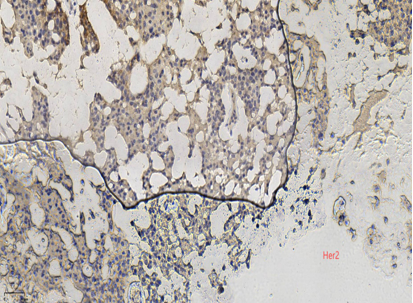

ER弥漫强+,Her2-,ki67低表达

具有神经内分泌表达:CgA、Syn(约70%的比例,阳性细胞表达不等)

CK5/6、CKH-,可斑驳性的残留

肌上皮内-,导管周可-可+